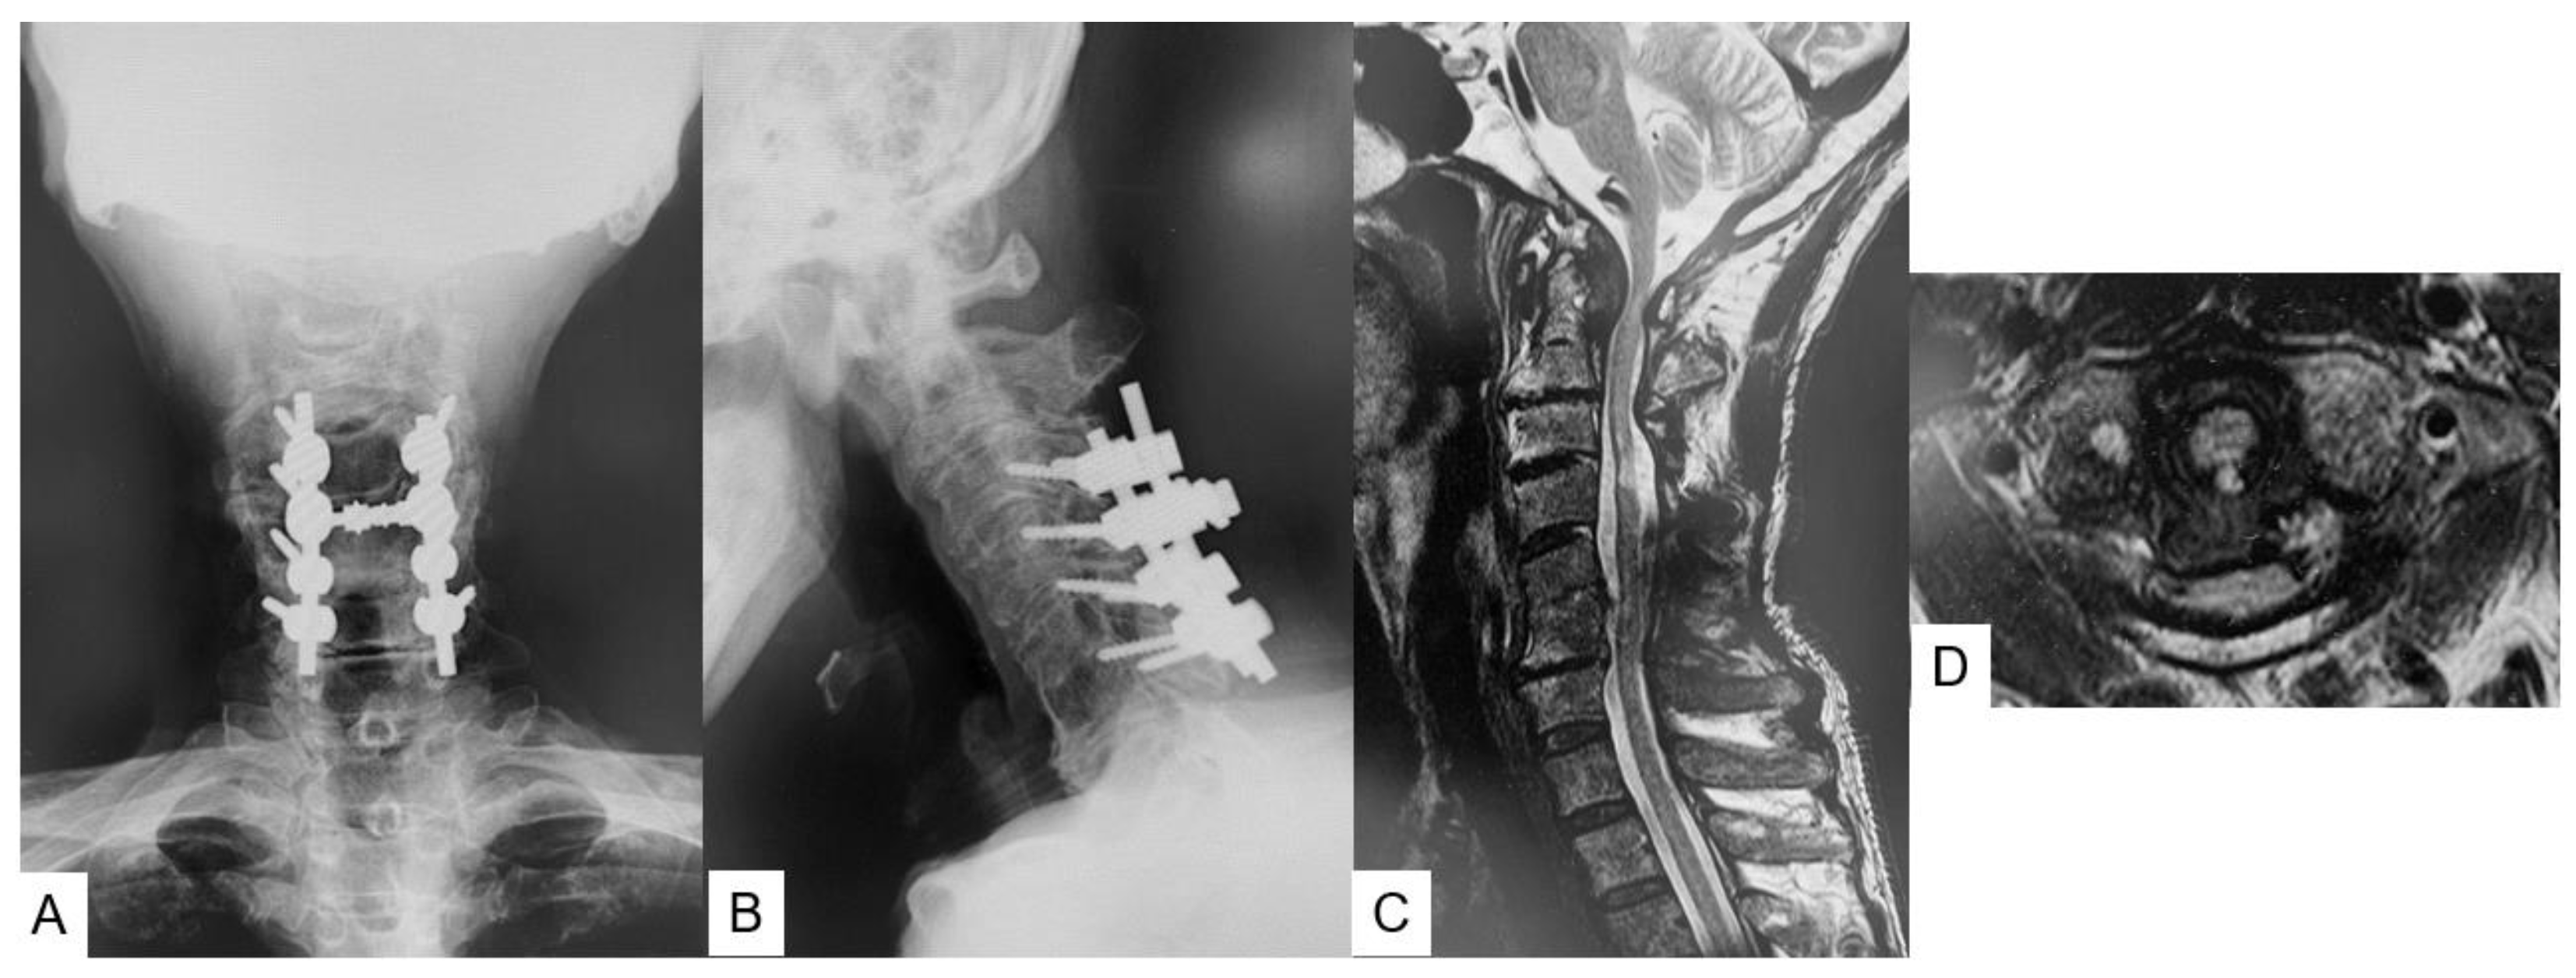

2.3. Preoperative Imaging

2.4. Surgery

2.5. Postoperative Imaging